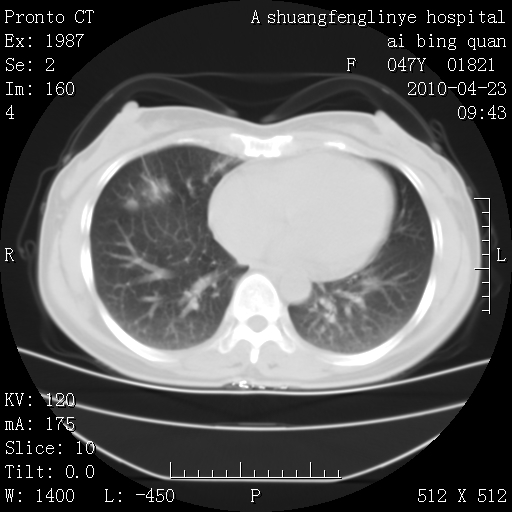

标题: CT25944:胸痛、气短、前几日高烧!肺Ca?请会诊! [打印本页]

标题: CT25944:胸痛、气短、前几日高烧!肺Ca?请会诊!

双肺多发结节,考虑转移瘤,肺癌肺转移不除外

周围型肺癌并肺转移

双肺多发结节,部分密度较高,最大结节边缘光滑。临床有“胸痛、气短、前几日高烧”病史。首选考虑:右肺感染性病变!建议积极消炎后复查!